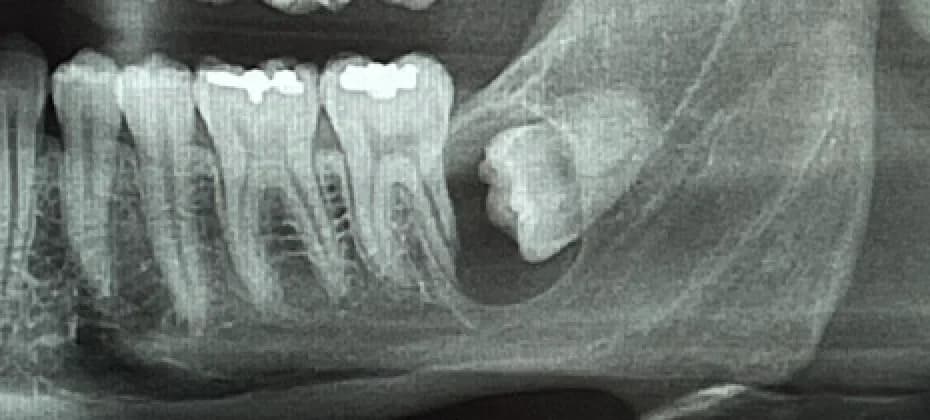

The extraction of wisdom teeth, also known as third molars, is a common dental procedure performed to remove teeth that cannot grow properly or cause dental problems. They are typically four in number and usually appear in the mouth between the ages of 15 and 25. They can fully erupt, be partially erupted, or be impacted. They typically do not have enough space in the mouth, so they are often misaligned and exert pressure on adjacent teeth, potentially causing damage. Extraction of wisdom teeth is often recommended when the teeth are impacted (trapped in the gum or bone) or causing problems such as pain, infection, tooth decay, shifting of other teeth, or the development of cysts. It is advisable to have them extracted at a young age, typically at the end of adolescence or early adulthood. Indeed, the risks increase with age, and recovery is easier at a younger age.